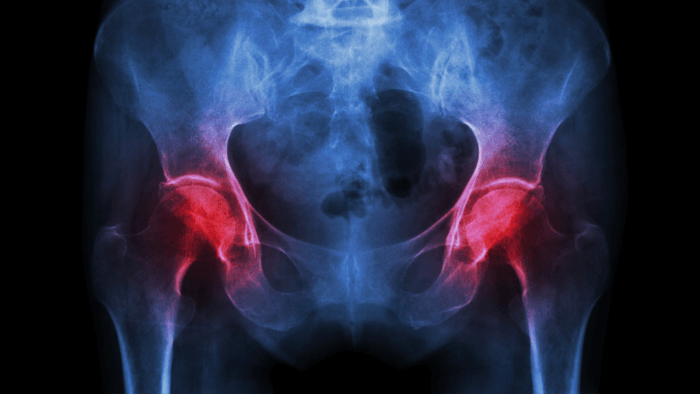

Why This Matters

hip joint x-ray showing osteoarthritis

When everything’s working as it should, your joints allow you to move through life with ease, whether you're going for a walk, dancing in your kitchen, or playing with your grandkids. But when arthritis strikes, it’s like throwing a wrench into a finely balanced system.

• Cartilage breaks down

• Inflammation invades the synovial lining

• Subchondral bone stiffens

• Supporting muscles and ligaments weaken

Understanding what’s going wrong at this structural level helps us not only grasp why arthritis hurts but also guides us in finding better ways to manage it, from medications and exercise to joint replacement or regenerative therapies. In the next few sections, we’ll home in on exactly how arthritis develops and progresses, what’s happening at the cellular and chemical level, and why catching it early (or even better, preventing it) can be life-changing.